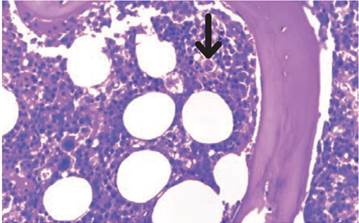

En laboratorios clínicos de referencia se pueden analizar los niveles del receptor soluble de la interleucina 2 (sIL2-R) o CD25, el cual es un marcador de la activación de linfocitos. Para su diagnóstico se precisan valores mayores a 2.400 UI/ml. La citometría de flujo se puede utilizar para evaluar la actividad de las NK, los niveles de perforinas en los LTc y el marcador de membrana de células citotóxicas CD107a, que hace parte de los gránulos que liberan Perf y Gz 1,29,44,45. En la biopsia de médula ósea se puede observar la presencia de eritrofagocitosis medular, hallazgo característico de la LHH 14; sin embargo, su ausencia no excluye el diagnóstico. En caso de una alta sospecha, se recomienda la toma de biopsias de médula ósea seriadas (Figura 2) 45. Adicionalmente, esta hemofagocitosis se puede observar en el tejido esplénico, hepático, renal, los ganglios linfáticos y la piel 14,44.